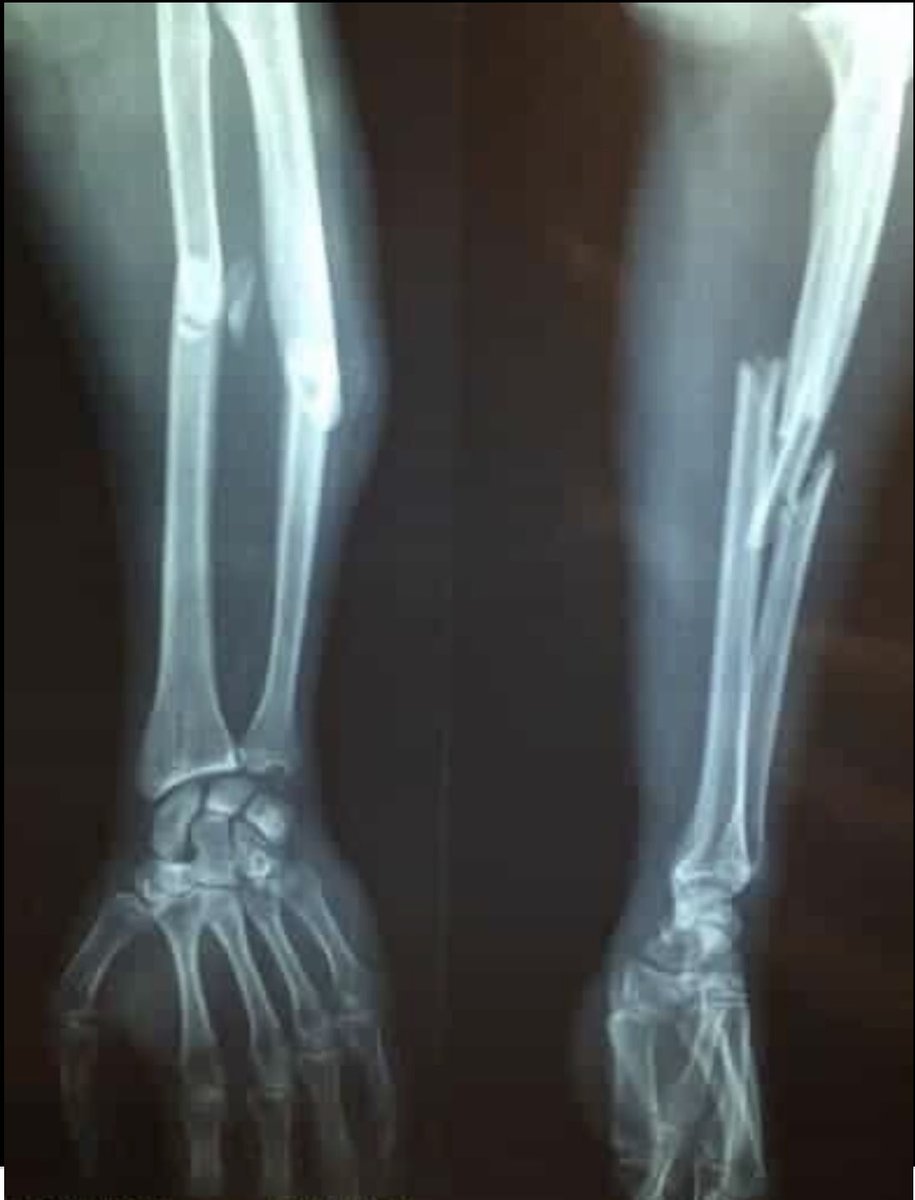

فمستوى التأهيل قد يكون تدريجي

فمثلا مدى حركة المفصل ونسبة الضغط على الطرف تزداد بشكل تدريجي بمرور الوقت تحت إشراف طبي

خلاصة الثريد..... هذه النقاط يفترض على كل مريض معرفتها بعد حدوث الكسر لا قدر الله ومناقشة الخطة التأهلية مع طبيبك